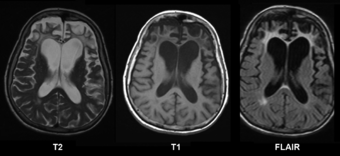

| Brain MRI of a 65-year-old female person with frontotemporal dementia. Cortical and white matter atrophy of the frontal lobes is clear in all images. |